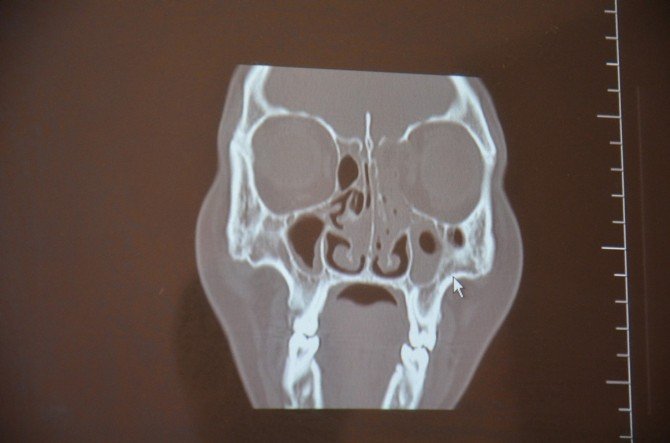

Konuyla ilgili bir açıklama yapan Mehmet Akif İnan Eğitim ve Araştırma Hastanesi K.B.B. Uzmanı Op. Dr. Ahmet Doblan, "Bulanık görme, çift görme ve baş ağrısı şikayetiyle hastanemiz K.B.B. kliniğine müracaat etmiş olan 36 yaşında Bedriye Uysal isimli hastada, yapılan muayene ve tetkikler sonucunda sol etmoid kemikten kaynaklanan ve yaklaşık 1 buçuk santim orbita içerisine uzanan ve orbitada itilmeye sebep olan kitlenin kafa tabanında ön kafa çukuruna da yaklaşık 1 santim kadar girdiği ve beyine doğru uzandığı görüldü. İntraorbital ve intrakranial uzanım gösteren etmoid osteom (kemik tümörü) teşhisi konulan hastaya endoskopik kafa tabanı ve orbita tümörü eksizyonu yapılması gerektiği, ameliyat olmaması durumunda körlük ve beyin zarlarında iltihaplanmaya bağlı menenjit riskinin olduğu anlatıldı.

Hastaya uygulanan medikal tedavinin ardından ameliyata hazır hale gelince yaklaşık 6 saat süren bir operasyonla sadece burun içerisinden girilerek tümör tamamen çıkartıldı. Bu ameliyat devlet hastanelerinde çok nadir olarak yapılan ve genellikle beyin cerrahi göz doktorlarının katılımıyla yüzde ve kafa derisinde kesilerle yapılan bir ameliyattır. Ancak biz burada bunu hiçbir kesi yapmadan baştan sona sadece endoskopik görüntülemeyle gerçekleştirerek ameliyattan sonra yoğun bakım ihtiyacı duymadan hastamızı servise çıkartmayı başardık. Ameliyat sonrası birinci günde çekilen görüntüleme tetkiklerinde hiçbir sorun olmadığı ve tümörün tamamen çıkartıldığı görülen hastanın tamponları alınıp hasta taburcu edildi" dedi.